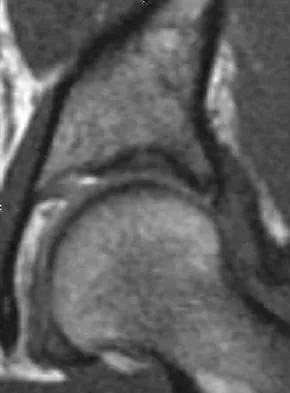

A 28-year-old man sustained numerous injuries in an accident including a dislocation of the elbow and a severe closed head injury that resulted in unconsciousness. The elbow was reduced in the emergency department. After 1 month of rehabilitation, the patient reports pain and stiffness. A radiograph is shown in Figure 23. Management should now consist of

Correct Answer: open reduction, heterotopic bone excision, anterior and posterior capsular releases, and a hinged elbow fixator.

In a young individual with a chronic dislocation of the elbow and heterotopic bone formation, the treatment of choice is open reduction, heterotopic bone excision, anterior and posterior capsular releases, and a dynamic hinged fixator to begin protected early postoperative range of motion. It is important to understand that the fixator protects the reconstruction and allows early range of motion, but it does not maintain the reduction and should not be expected to do so. Pin fixation across the elbow delays early motion and is not recommended. Total elbow arthroplasty is not indicated, and ulnohumeral arthroplasty is for a primary arthritic condition. Garland DE, Hanscom DA, Keenan MA, et al: Resection of heterotopic ossification in the adult with head trauma. J Bone Joint Surg Am 1985;67:1261-1269.